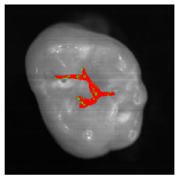

The classification model generated by the fine kNN algorithm was used to classify the fissural systems of five additional teeth, which were not included in the training and evaluation of the algorithm (Table 3). The projection maps show that the classified enamel state is in good agreement with the PLM images in the histologically validated area: Stained samples show a nearly homogeneous distribution of the predicted enamel state “stained”. However, some clearly circumscribed regions away from the histologically validated area are classified as “stained lesion”. Stained lesion samples exhibit a more heterogeneous distribution of enamel health states: A large proportion of fissural areas are classified as “stained lesion”; however, there are numerous “stained” regions of varying sizes dispersed in between.

Table 3.

Clinical simulation of enamel health predictions using HSI-based automated classification as a decision-support system. Five additional teeth (two stained [(a) and (b)], three stained lesion [(c) through (e)]) were imaged and classified by the previously trained fine kNN classification algorithm (i.e., the samples in this table were not included in algorithm training). Stained sound enamel is displayed green, whereas lesions (stained or unstained) are displayed red. Polarization microscopy images from each tooth’s sectional plane (dotted lines) serve as reference. All scale bars = 1 mm.

The results in this study are based on the simplified assumption of a homogeneous distribution of the occlusal health state that was histologically determined at the central region of the fissure. Occlusal caries originates from the fissure in the vast majority of cases. The part of the fissure that clinical experience showed to be the most questionable part (i.e., the most likely to be carious) was selected for further analysis in this study, as this is the clinically most relevant issue. As caries is a dynamic process, however, occlusal classification images show heterogeneous enamel health states (Table 3). Lesions may develop in one or more sites of the fissure and subsequently spread to further areas. Hence, it is likely that some parts of an analyzed tooth are still unaffected, whereas others contain lesions of varying extent. Thus, teeth showing sound but stained enamel in the histological cross-sectional plane may show lesions in other parts of their fissure (Table 3a,b). On the other hand, histologically carious teeth show still unaffected fissural regions (Table 3c,e). In order to refine the validation process, further cross-sections from different parts of the tooth’s fissural system should be considered. Occlusal caries originating from outside the fissure are rare and pose no pertinent clinical issue. In close proximity to the histologically validated areas, the HSI-based classification results show very good agreement with the reference occlusal health state determined by PLM of ground sections (MCC = 0.75).